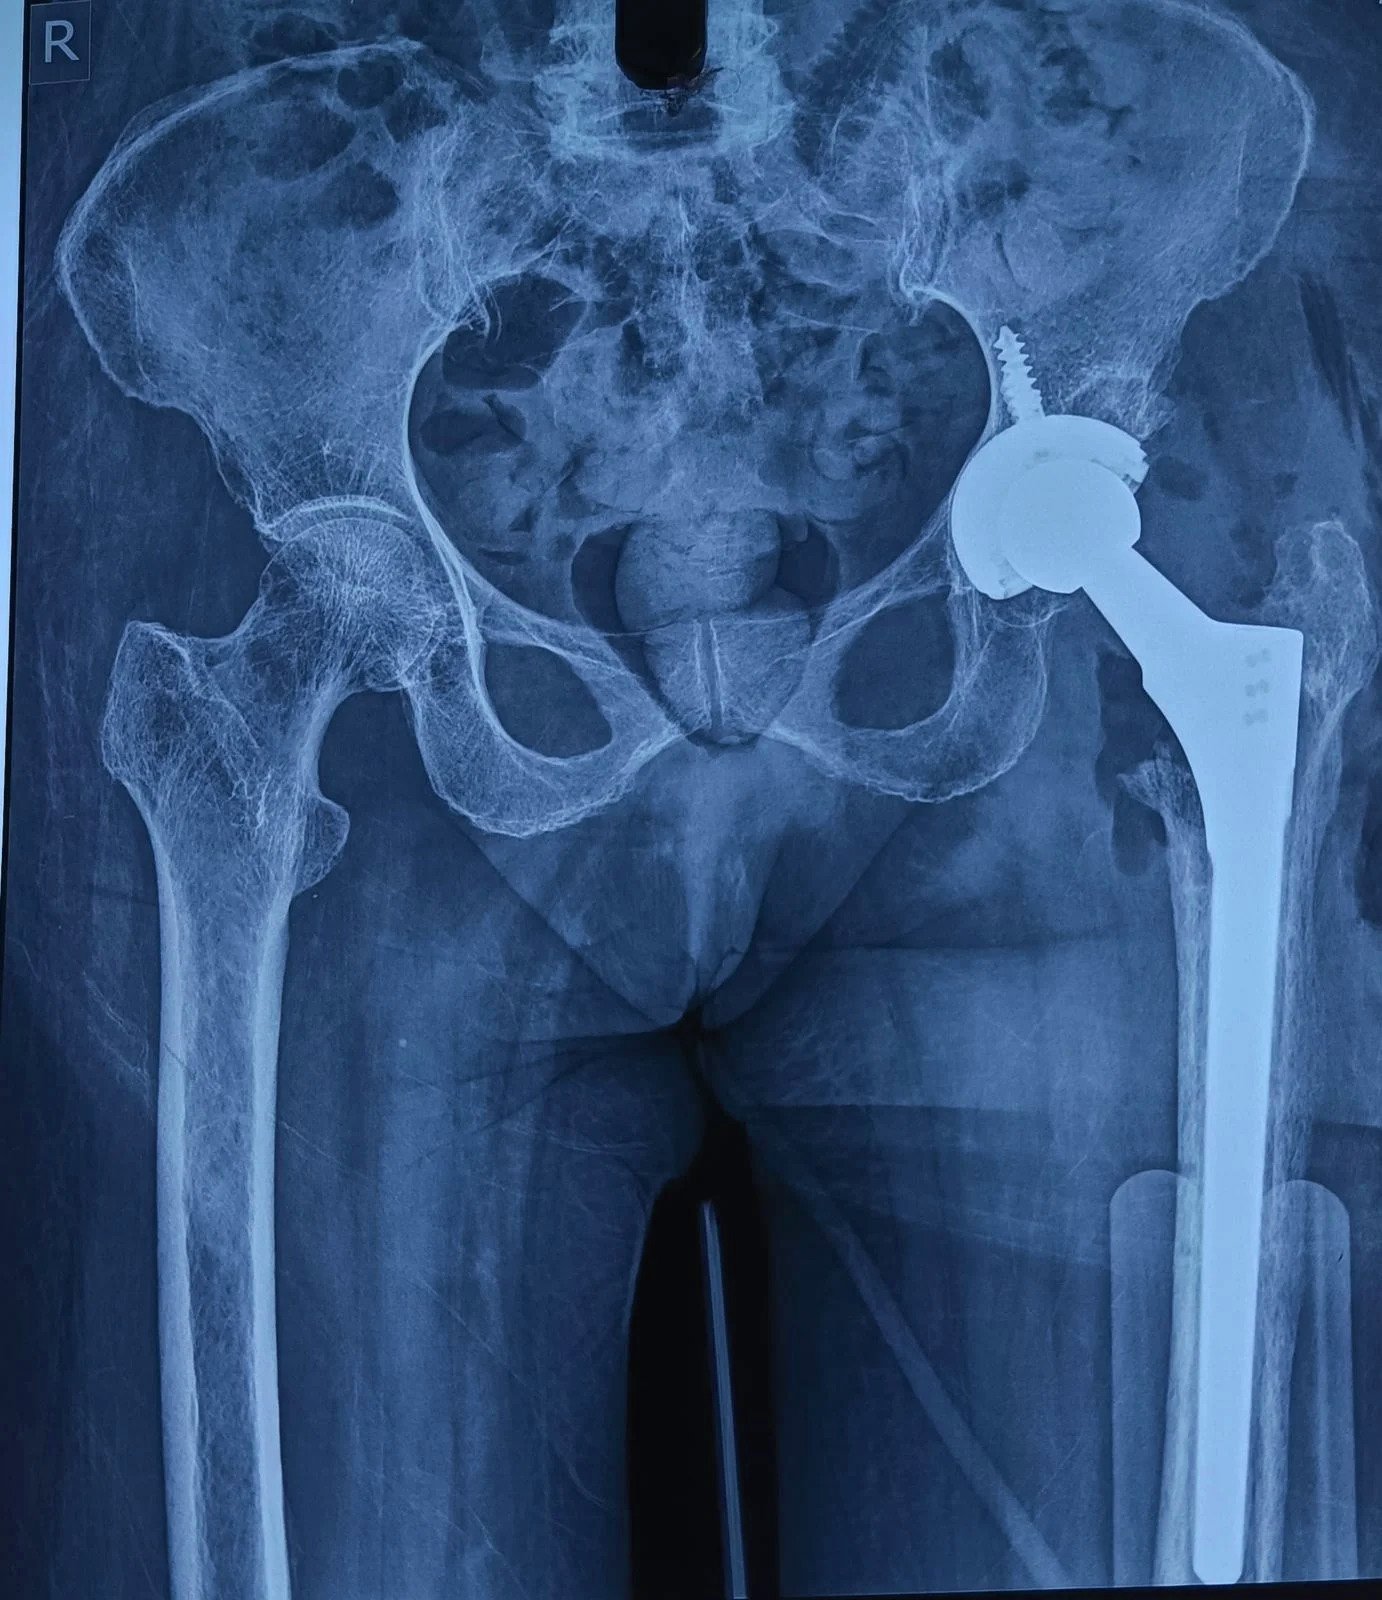

DHS Failure & Long Stem THR

Post-Op X-Ray